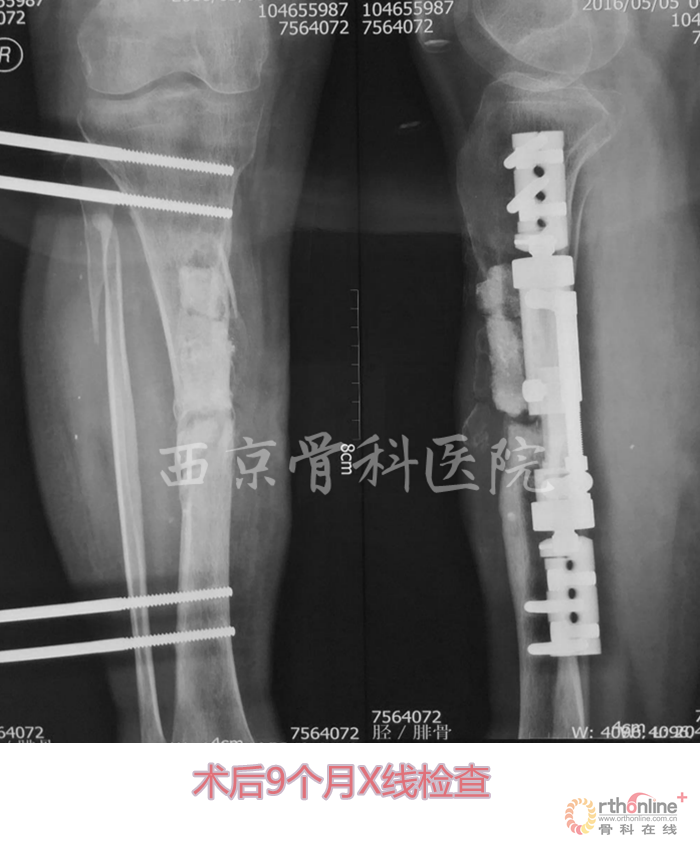

术后,他们按照组织工程再生骨临床转化应用方案定期进行血液指标、免疫指标和影像学指标的检测复查,患者术后3个月即可扶拐下地行走,术后6个月可弃拐逐步下地负重行走,12个月拆除已使用了2年的外固定支架,行走及下肢关节活动如常,恢复了正常的生活与劳动能力。